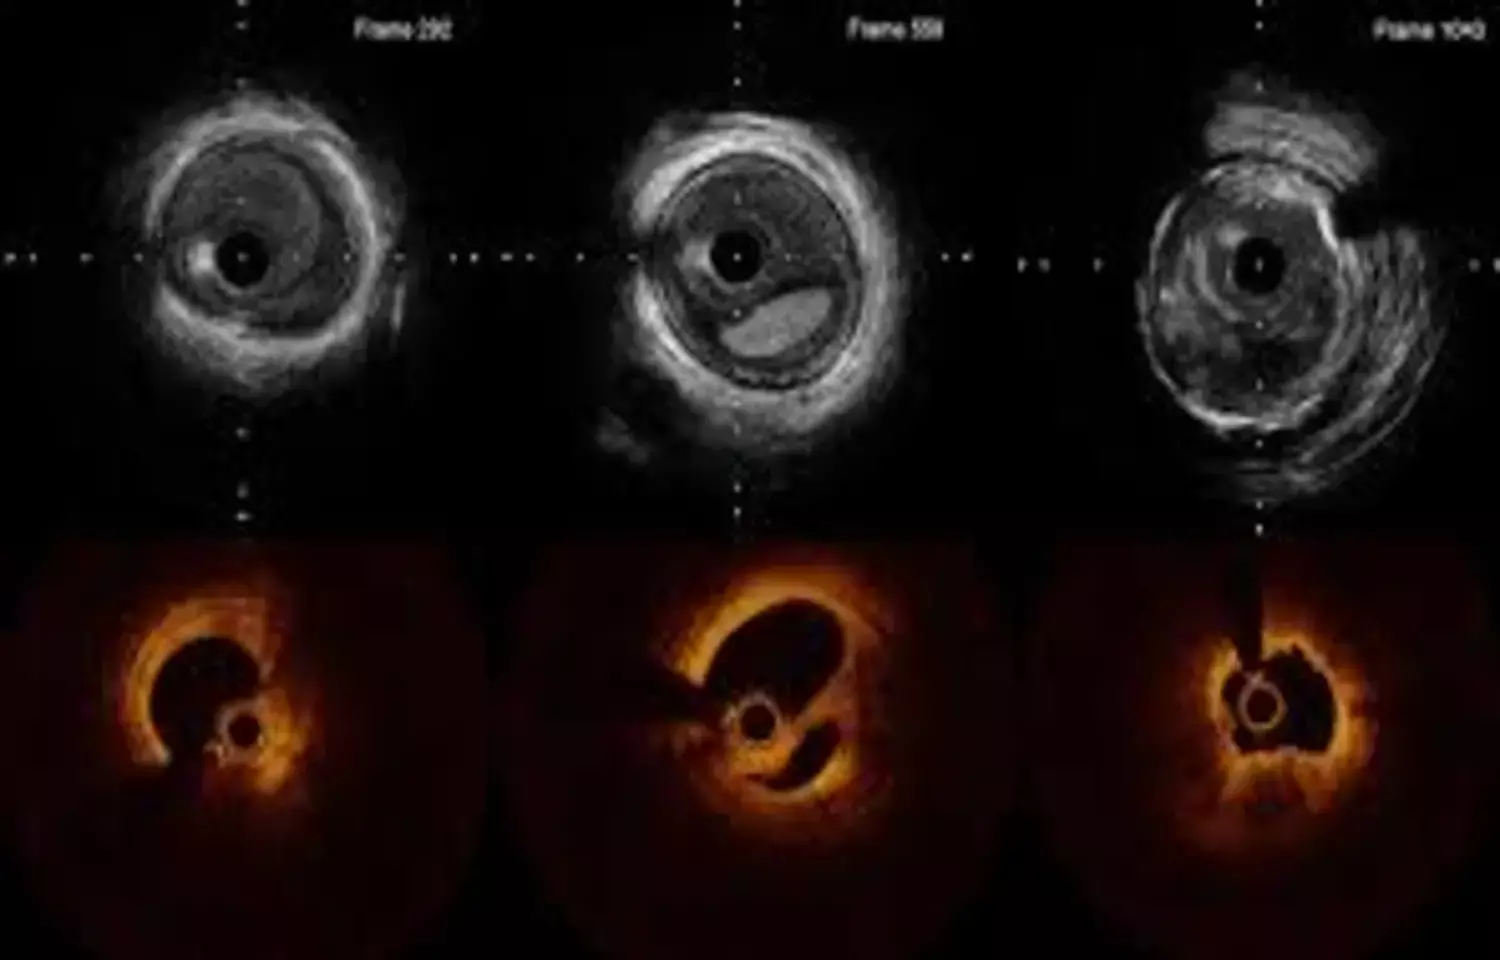

Five-year follow-up data from the RENOVATE-COMPLEX-PCI trial show that intravascular imaging-guided percutaneous coronary intervention leads to better clinical outcomes in patients with complex coronary lesions. Earlier results (median follow-up 2.1 years) demonstrated a 36% relative reduction in target-vessel failure-including cardiac death, target-vessel myocardial infarction, or clinically driven target-lesion revascularization-compared with angiography-guided percutaneous coronary intervention. In addition, target-vessel MI or cardiac death decreased by 37%, and cardiac death alone by 53%, highlighting the long-term benefit of intravascular imaging guidance.

Data regarding long-term outcomes of intravascular imaging-guided percutaneous coronary intervention (PCI) for complex coronary artery lesions, compared with angiography-guided percutaneous coronary intervention, remain limited.

The authors sought to present long-term clinical outcomes of intravascular imaging-guided percutaneous coronary intervention compared with angiography-guided percutaneous coronary intervention in patients with complex coronary artery lesions. Eligible patients with complex coronary artery lesions were randomly assigned 2:1 to undergo intravascular imaging-guided percutaneous coronary intervention or angiography-guided percutaneous coronary intervention in this prospective multicenter open-label superiority trial performed in South Korea. The primary endpoint was a composite of cardiac death, target vessel-related myocardial infarction, or clinically driven target vessel revascularization.

Results: A total of 1,639 patients underwent randomization with 1,092 assigned to imaging-guided percutaneous coronary intervention and 547 assigned to angiography-guided percutaneous coronary intervention. At a median follow-up of 5.3 years (Q1-Q3: 4.4-6.2 years), the primary endpoint occurred in 109 of 1,092 patients (10.5%) in the intravascular imaging-guided percutaneous coronary intervention group and 78 of 547 patients (14.9%) in the angiography-guided percutaneous coronary interventiongroup (HR: 0.68; 95% CI: 0.51-0.91; P = 0.009).

Cardiac death or target vessel–related myocardial infarction occurred in 78 patients (7.6%) in the intravascular imaging-guided percutaneous coronary intervention group and in 56 patients (10.7%) in the angiography-guided percutaneous coronary intervention group, clinically driven target vessel revascularization in 45 (4.4%) and 32 (6.2%), and definite stent thrombosis in 1 (0.1%) and 4 (0.7%), respectively. There were no apparent differences in procedure-related safety events between the groups.

In patients with complex coronary artery lesions undergoing percutaneous coronary intervention, intravascular imaging guidance reduced the risk of a composite of cardiac death, target vessel–related myocardial infarction, or clinically driven target vessel revascularization at median follow-up of 5.3 years, compared to angiography guidance.